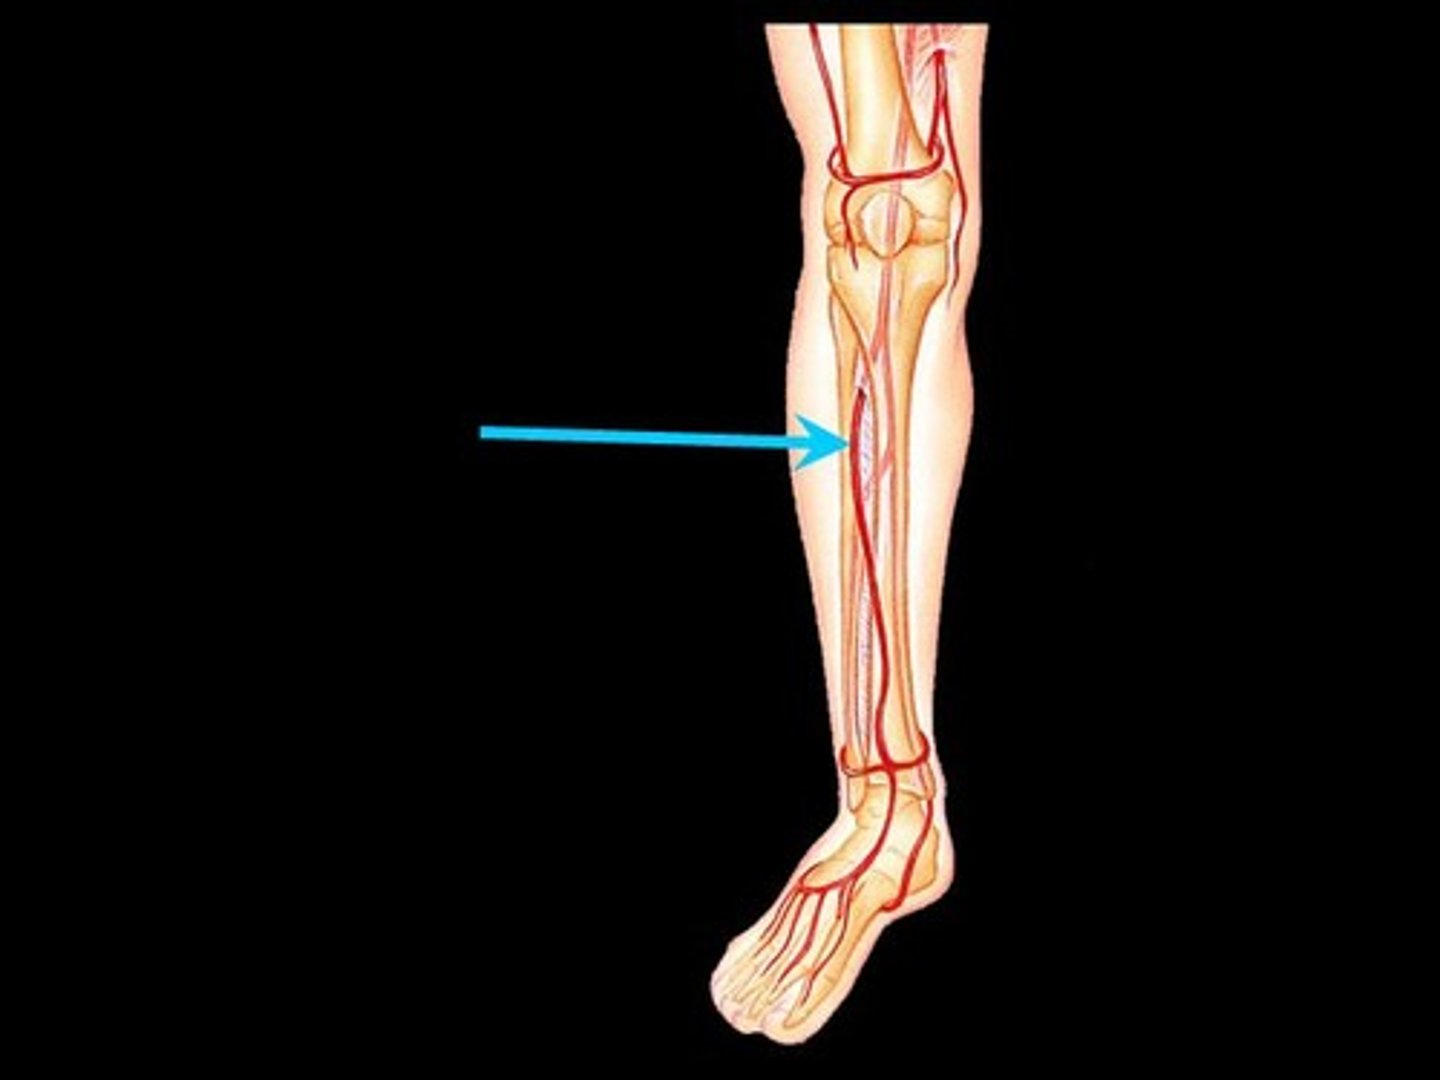

Anterior tibial artery

artery

Posterior tibial artery (in tarsal tunnel)

artery

Dorsalis pedis artery